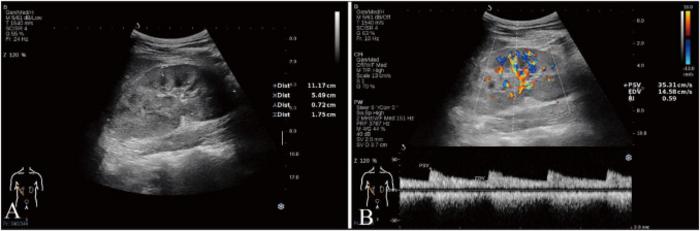

Efficient clinical management of chronic kidney disease (CKD) is crucial for public health, as it is a progressive condition that affects 10% of the global population. Early diagnosis and active monitoring play a vital role in effectively treating and prognosing the common pathological pathway from CKD to end-stage renal disease (ESRD), which is characterised by renal fibrosis. Researchers from the Department of Health Technology and Informatics of the Hong Kong Polytechnic University (PolyU) have developed Smart-CKD (S-CKD), a computer-aided diagnostic tool. It integrates ultrasound (US) data and selected clinical variables to provide clinical insights and assesses the risk of moderate-to-severe renal fibrosis progression in CKD patients.

Specifically, S-CKD integrates three pivotal clinical parameters - age, ultrasonic renal length, end-diastolic flow velocity of the interlobar renal artery - which could be collected through regular clinical follow-ups. By leveraging machine learning, S-CKD integrates these data, resulting in a promising diagnostic efficiency of 80%.

The diagnostic field of renal fibrosis has seen remarkable progress with ultrasound elastography. However, this diagnostic modality highly depends on the operator’s experience and technical proficiency, which poses challenges for implementation, particularly in resource-limited areas. The primary aim of inventing S-CKD is to enable easy and ubiquitous applications in clinical management, even in the face of resource constraints. The input variables for S-CKD can be readily obtained from medical records and routine imaging assessment at a low cost, while the output probability can accurately and dynamically stratify patient risks. This established tool provides accurate information for patient-centered, informed decisions regarding the clinical management of CKD progression through active surveillance and non-invasive assessment.